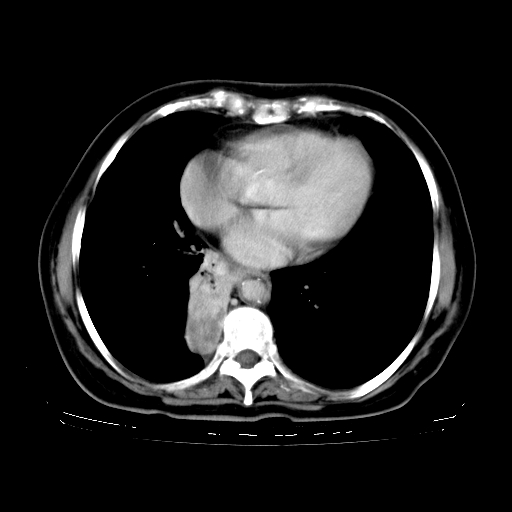

女,70岁,咳嗽、咳痰一个月,低热一周。

2.胸主动脉夹层。

4、主动脉夹层。

5、右侧少量胸腔积液。

支持,首先一元论解释。胸主动脉部分层面环形低密度,中心强化。环形影不强化。不象真假腔的改变。我考虑动脉炎,不太支持夹层动脉瘤-和大家的观点不一致,希望楼主让患者再做个心血管的彩超吧。